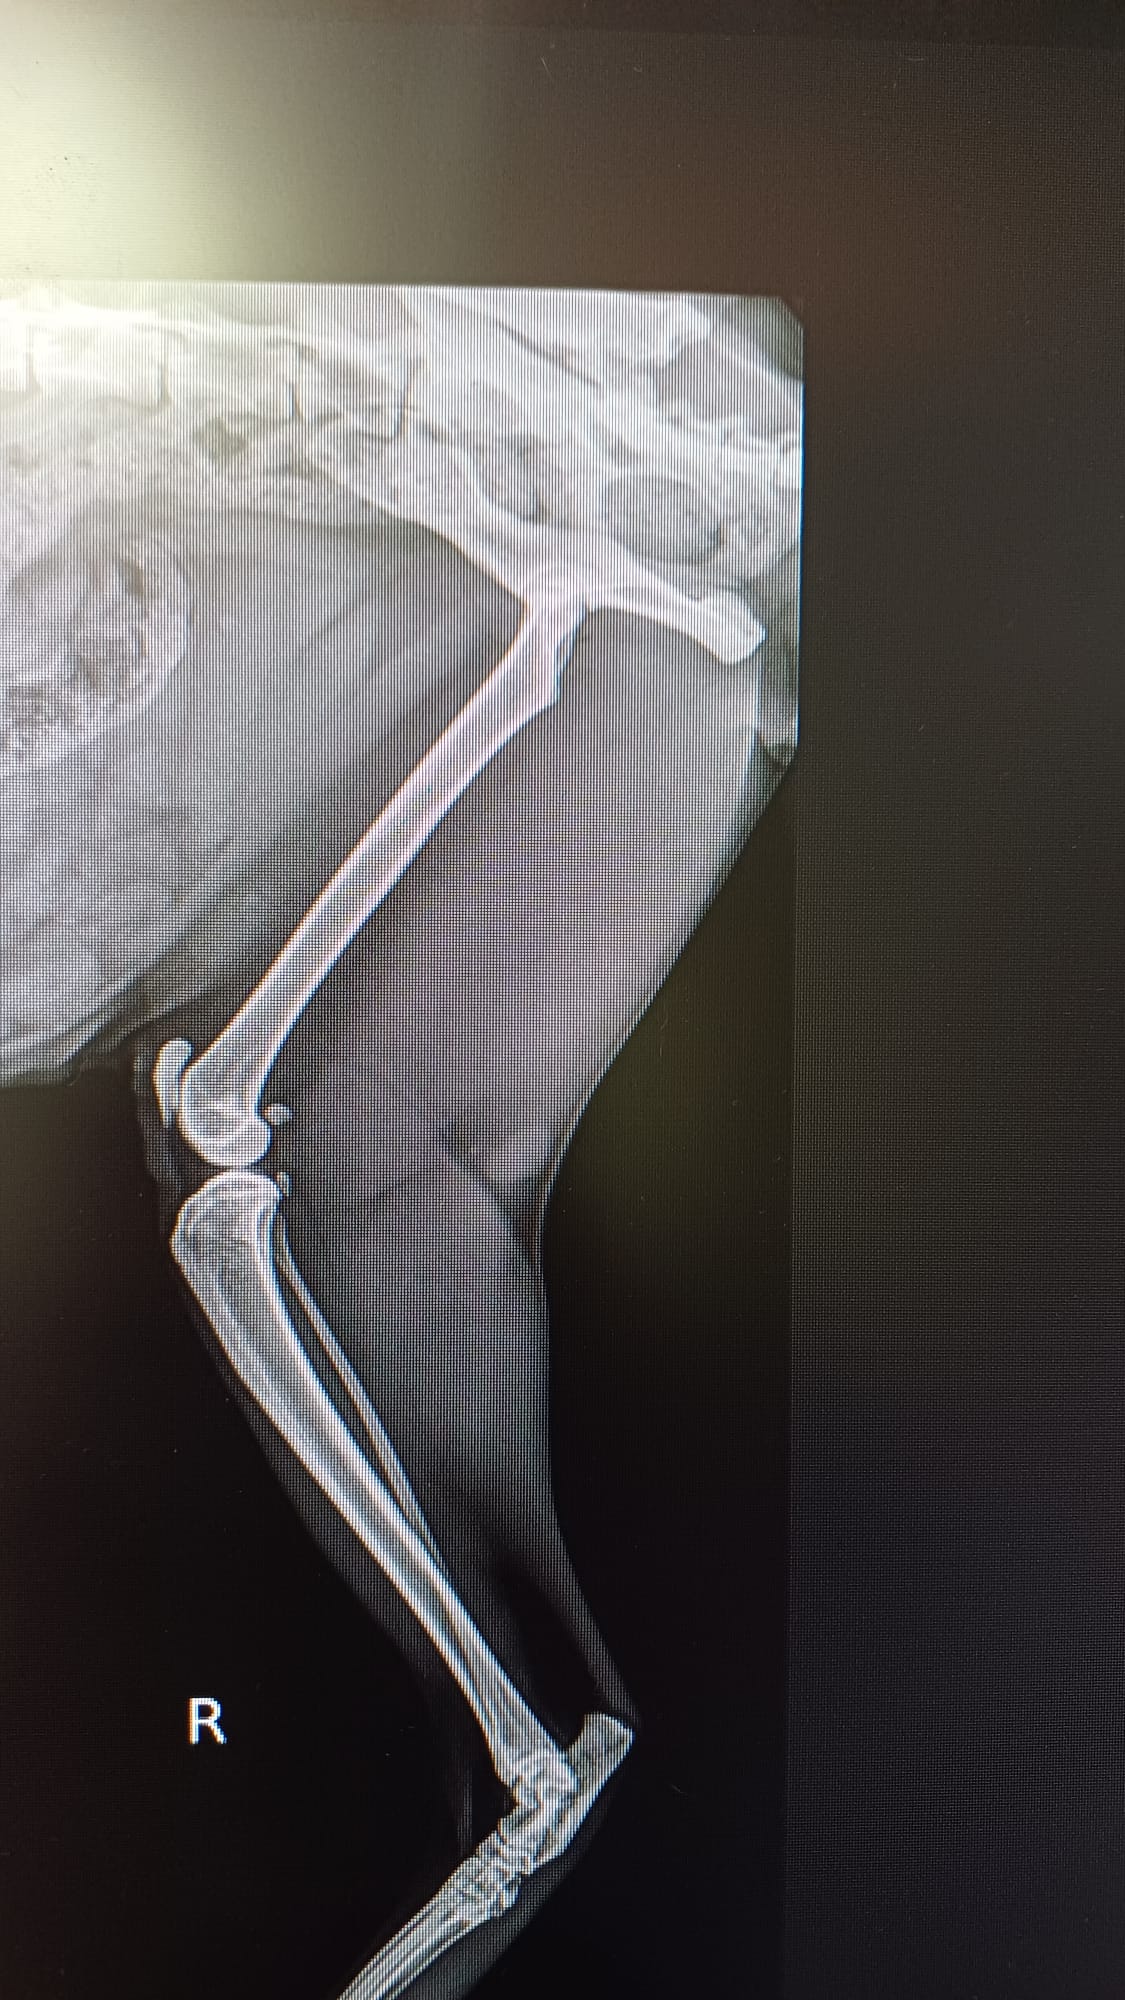

En septiembre cuando subimos a realizar las fotos del calendario vimos que no tenia masa muscular en una de las patas traseras, además de una cojera bastante importante. Nos lo llevamos a nuestros veterinarios donde se vio que tenia una Fractura antigua de la cabeza del femur. Al día siguiente se le realizo una artroplastia de la cabeza del femur. Ahora guarda reposo relativo en nuestro refugio. Es un gato adorable que nos ha robado el corazón desde el minuto 0.